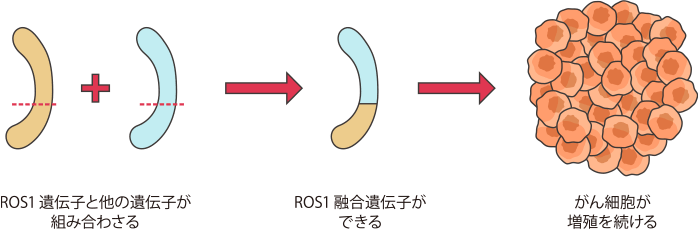

ROS1融合遺伝子は、ROS1遺伝子とさまざまな遺伝子が融合したものです。この組み合わさったROS1融合遺伝子からできるタンパク質により、がん細胞を増殖させるスイッチが入り、がん細胞が限りなく増殖してしまう働きがあることがわかってきました。

ROS1融合遺伝子は、非小細胞肺がんの約1~2%に認められます。

体内で細胞を増やしたり(増殖)、新しい機能をもった細胞に変化したりするときに働く遺伝子の1つにROS1遺伝子があります。ROS1遺伝子に何らかの異常があると、他の遺伝子と組み合わさって特殊な遺伝子ができることがあります。この特殊な遺伝子をROS1融合遺伝子といいます。

ROS1融合遺伝子はROS1遺伝子と組み合わさる遺伝子の種類によっていくつかの種類があることが確認されています。

ROS1融合遺伝子はがん細胞を増殖させる

ROS1融合遺伝子は、肺がん(非小細胞肺がん)の患者さんのうち約1〜2%の患者さんで見つかっています。また、ROS1融合遺伝子が見つかる肺がんの患者さんは、若年の方、女性、非喫煙者に多いことがわかっています。

ROS1融合遺伝子ができると、がん細胞を増殖させるスイッチが入ったままになり、がん細胞が増殖を続けます。

ROS1融合遺伝子は、EGFR遺伝子変異やALK融合遺伝子の検査と同時に検査を行うことが推奨されています。